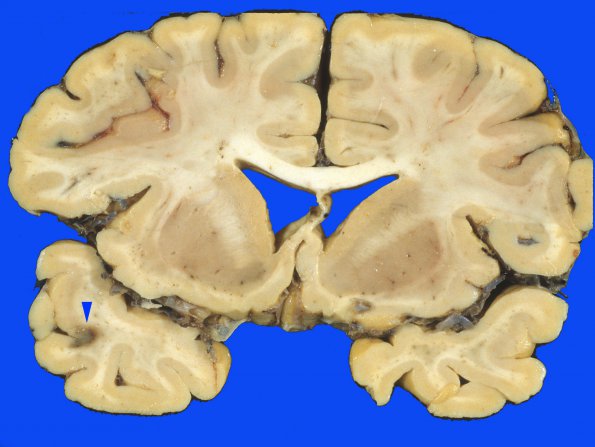

3A1,2 One telangiectasia/DVI is found in the left temporal cortex,(arrowhead, 3A1) and at higher magnification in 3A2